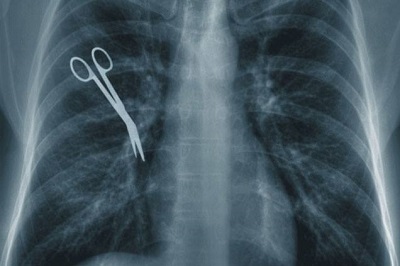

Es que, a consecuencia de estos casos de negligencia, muchas vidas son perjudicadas, tanto de muerte, como de ser gravemente lastimadas; cuántos casos no hemos oído sobre pacientes que les amputan un órgano que no debía ser amputado. Destruir una vida de esa manera, no debería siquiera cuestionarse.